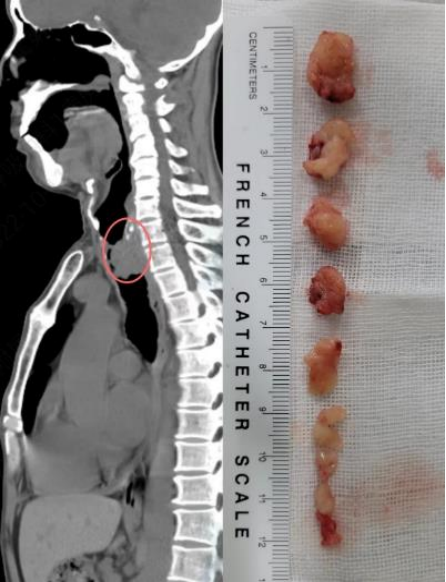

床旁支气管镜可以快速解除中心气道阻塞,适用于:①气道内异物,包括分泌物、积血以及其他异物(图1);②良性病变。例如感染、良性肿瘤或增生、气道支撑结构的破坏等(图2);③恶性病变,例如气道内肿瘤组织堵塞、气道壁浸润以及管腔外的压迫(图3)

图片

4. 难治性气胸以及气管、支气管瘘的腔内封堵

各种类型的气胸经持续肋间引流7 d后仍存在活动性漏气时称为难治性气胸。支气管镜可以选择性地将通向胸膜瘘口(或称破裂口)的责任引流支气管可逆性封堵,以阻断或明显减少胸膜瘘口的漏气量,进而使患侧肺复张并加速胸膜瘘口愈合(图4)

图4  X线胸片示球囊导管填塞治疗机械通气合并难治性气胸